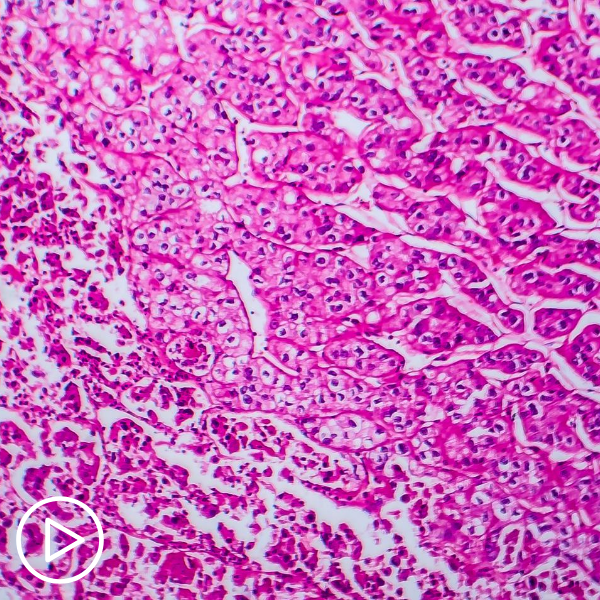

What is Renal Medullary Carcinoma?

This video was originally published by Diverse Health Hub. What is Renal Medullary Carcinoma? from Diverse Health Hub on Vimeo. What is renal medullary carcinoma (RMC)? Dr. Pavlos Msaouel, a…